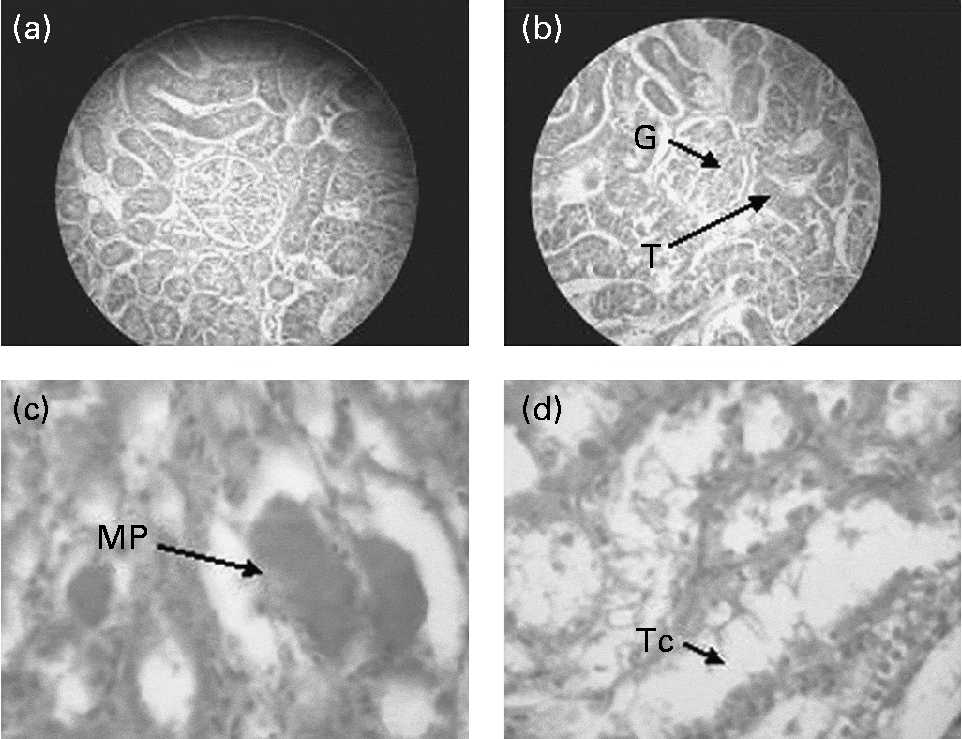

Influence of dietary finger millet seed coat matter on the